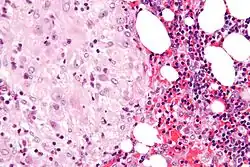

Acute choriodeciduitis, with neutrophils seen in the chorion and decidua.